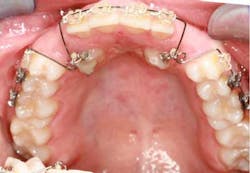

When a full permanent dentition is present (with the exception of impacted canines), the labial/palatal position of the canine will have an influence on what the provider can do. (1) Arguably, obtaining a CBCT is considered mandatory and will allow for a more inclusive treatment plan creation. If angulation is favorable, then consideration to remove the primary canine and wait six months to see if there is movement of the permanent canine is an option. If extraction of the canine(s) is needed, then a premolar substitution, which is dependent on occlusion, can be used in the space. An implant can also be an appropriate alternative. When pulling a canine into the occlusal arch, there is risk involved. Trauma to adjacent teeth (root resorption) and ankylosis are some of the most common complications.The patient was put in full orthodontics and referred to a surgeon for extraction of the primary canines, exposure, and placement of retention on the impacted canines to pull them directly down from their current position.

A ballista appliance was used to prevent a facial pull of the canines in order to avoid and prevent resorption of the roots of the lateral incisors. As movement progressed over the course of the next year, eruption of the canines was considered a success. Once in position, they will be pulled facially into occlusion.